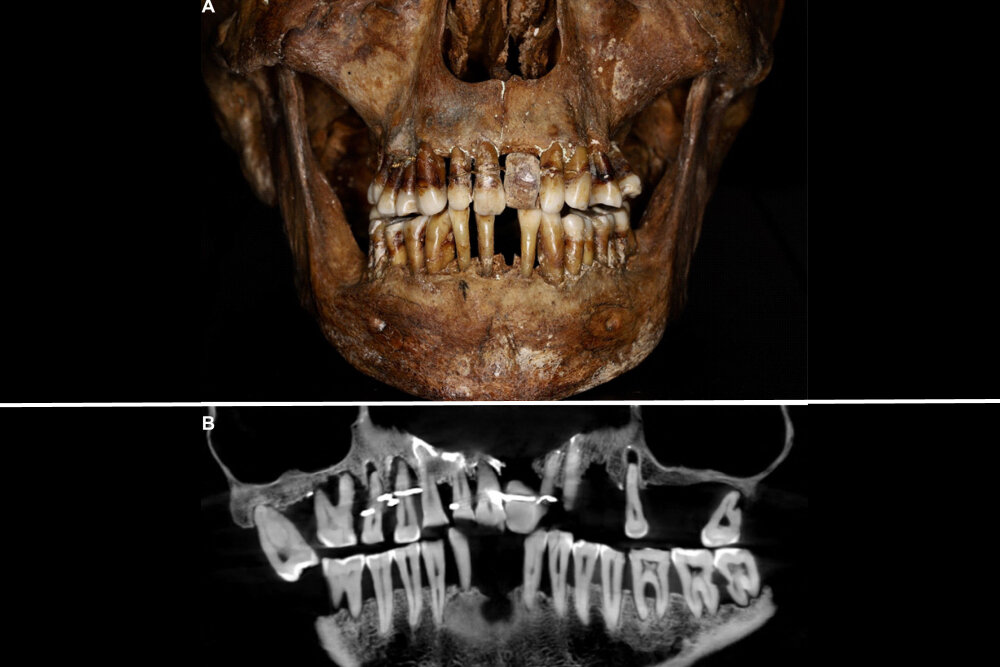

Тело французской аристократки Анны д'Алегри, умершей в 1619 году, обнаружили во время археологических раскопок в замке Лаваль на северо-западе Франции. Ее скелет и зубы, забальзамированные в свинцовом гробу, сохранились на удивление хорошо.

Тогда, в 1988 году, ученые обратили внимание на то, что у нее был зубной протез. У археологов еще не было передовой техники, чтобы просканировать протез и узнать побольше о ее здоровье. Спустя 35 лет исследователи установили, что д'Алегри страдала пародонтитом, из-за чего расшатывались ее зубы.

Аристократка использовала золотую проволоку, чтобы предотвратить выпадение зубов. У женщины также был искусственный зуб из слоновой кости, хотя 400 лет назад в моде были зубы гиппопотама. «Это не только терапевтическая помощь — исследование также показывает важность внешнего вида для аристократок, особенно для вдов и женщин, испытывающих большой стресс», — пишут авторы работы.

Фото: East News